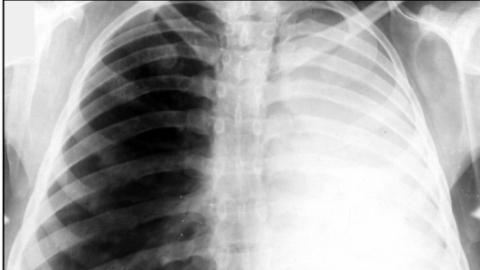

Ателектаз легкого — симптомы и диагностика . Симптомы ателектаза легкого очень часто зависят от степени поражения и быстроты развития заболевания .

Компрессионный ателектаз, или коллапс, легкого . Это состояние вызывается сдавлением легочных тканей снаружи, а также скоплением в плевральной полости экссудата, воздуха, крови или гноя .

Ателектаз легкого — это спадение какого-либо участка легочной ткани, возникающее вследствие сдавливания легкого извне либо закупорки просвета бронха . . . . фото, симптомы у взрослых, лечение . . .

Ателектаз — это спадение всего легкого (коллапс) или его части вследствие нарушения вентиляции, обусловленной обтурацией бронха или сдавлением легкого .

Ателектаз легкого — это патологическое состояние, при котором целое легкое или его часть спадается (происходит сближение и сжатие стенок легкого, при этом воздух из данного участка выходит) и выключается из . . .

Ателектаз легкого: на рентгеновском снимке или что это такое у взрослого, лечение дисковидной патологии или причины ее появления . Ателектаз - патологическое состояние, при котором ткань . . .